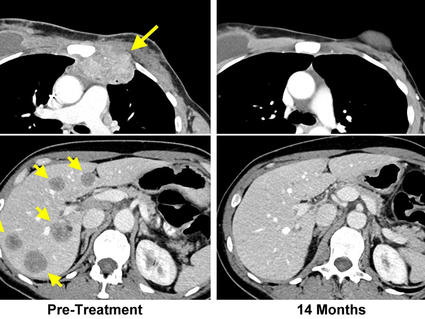

First, the researchers examined paired samples of primary and metastatic tumors from 17 women with breast cancer that had spread to their liver or lungs. Both primary and metastatic tumors were desmoplastic, and the metastatic tumors had nearly no cancer-killing immune cells, they found.

Compared with the other treatments, plerixafor plus the checkpoint inhibitors led to fewer cancer-associated fibroblasts, less desmoplasia, and more cancer-killing immune cells in the metastatic tumors. The combination of plerixafor and checkpoint inhibitors also decreased lung metastases and extended how long the mice lived.

In all three models, the researchers noted, several mice treated with plerixafor and checkpoint inhibitors had long-term remissions, doubling the rate of long-term remissions observed for immune checkpoint inhibitors alone.